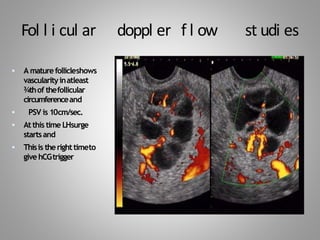

Fol l i cul ar doppl er f l ow st udi es

 A maturefollicleshows

vascularityinatleast

¾thof thefollicular

circumferenceand

 PSV is 10cm/sec.

 Atthis time LHsurge

startsand

 Thisis therighttimeto

givehCGtrigger

Fol l icul ar doppl er f l ow st udi es  A maturefollicleshows vascularityinatleast ¾thof thefollicular circumferenceand  PSV is 10cm/sec.  Atthis time LHsurge startsand  Thisis therighttimeto givehCGtrigger